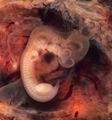

Mimoděložní těhotenství

Ektopické jinak též mimoděložní těhotenství je stav, kdy se po početí oplozené vajíčko uhnízdí jinde než v děloze. Z 95 % se jedná o vejcovod, v tom případě mluvíme o tubárním těhotenství, vzácně pak dochází k uhnízdění v děložním hrdle, vaječníku (3 %) či břišní dutině (1,5 %).[1] Jelikož jsou příznivé podmínky pro správný vývoj embrya pouze v děloze, dochází mimo dělohu často k jeho odumření. V případě vývoje embrya hrozí riziko krvácení, prasknutí vejcovodu a sepse. Ektopické těhotenství je pro ženu velmi nebezpečné a pokud není dostatečně rychle podchyceno, může skončit její smrtí.[1]